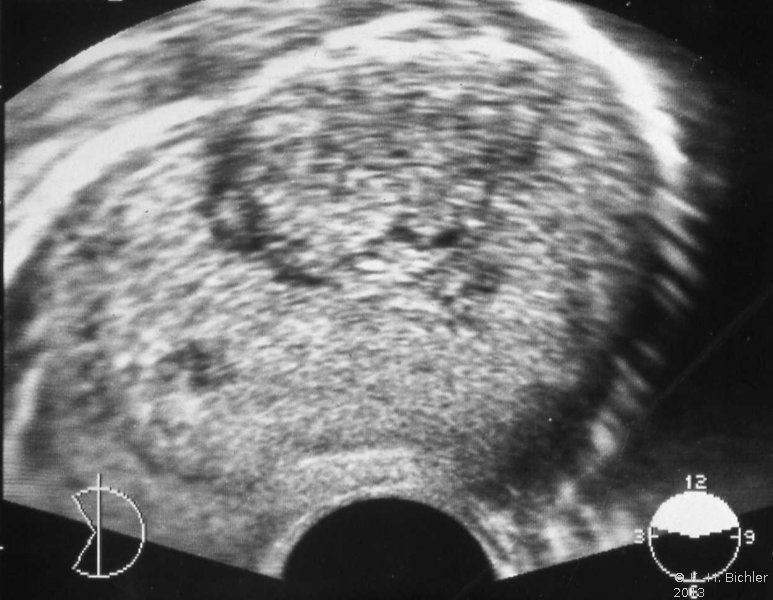

Der Patient kam wegen Schmerzen und Schwellung im rechten Hoden zum niedergelassenen Urologen. Die Untersuchung ergab palpatorisch Verdacht auf Tumor im rechten Hoden. Sonographisch fand sich ein umschriebenes, tumorverdächtiges Areal (

s. Abbildung 10a). Die Tumormarker waren erhöht: AFP 390 ng/ml und hCG 12,3 mIU/ml (Abbildung 9).

Die Hodenfreilegung ergab im Schnellschnitt ein embryonales Karzinom mit Teratomanteilen vom intermediären Typ und Dottersacktumor. Das Organpräparat zeigte auf der Schnittfläche einen umschriebenen Tumor von heterogener Struktur: Einblutungen, zystische Areale, gallertige Formationen (Abbildung 10).